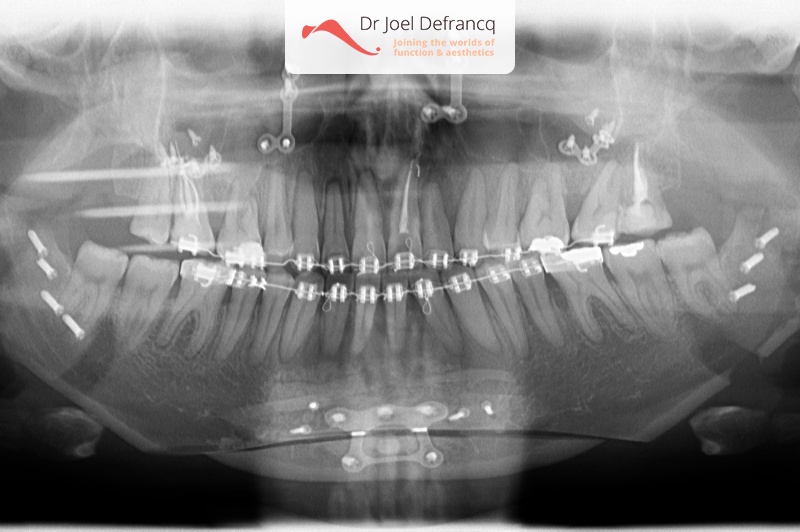

Schila: Open Beet

Diagnose van het gezicht

- Asymmetrisch gezicht

- Open beet

Dentale diagnose

Kaakchirurgie

- Vertikale verkorting bovenkaak (Le Fort I)

- Kinchirurgie

Esthetische chirurgie

- Neuscorrectie (rhinoplasty)